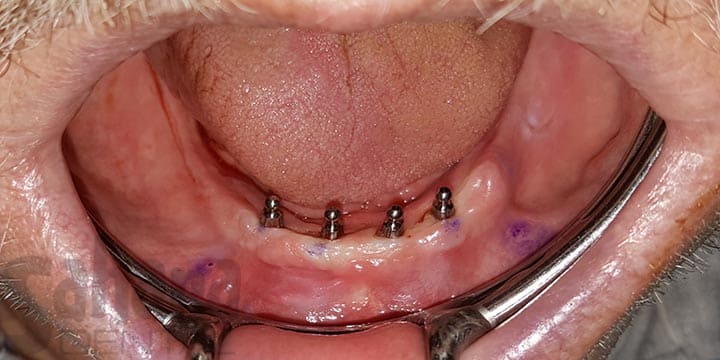

Secure Denture with 4 Mini Implants

Four mini dental implants were placed by Dr. Jamal in Hemet, California to securely anchor a lower denture. This treatment provides a stable, comfortable, and long-lasting solution — eliminating the slipping and discomfort often associated with traditional dentures.